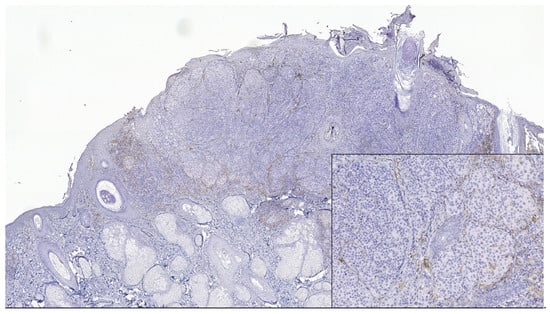

Figure 1. In nodular polypoid melanoma, CD4 intense membranous expression in intra and peritumoral lymphocytes (CD4 monoclonal antibody, clone EP204). In the lower left side detail, obx200.

PD-L1 (+) patterns associated with moderate to severe CD8+ and CD4+ lymphocytes intensities (CD8+TILs: 69.57%; MTCs: 75.00%; CD4+TILs: 97.30%; MTCs: 85.71%) compared to mild (CD8+TILs: 2.79%; MTCs: 7.14%, CD4+TILs: 0.00%; MTCs: 3.57%, p < 0.05) were observed in the majority of morphological types of melanomas (Table 2) (Figure 1, Figure 2, Figure 3, Figure 4 and Figure 5). Melanomas negative for PD-L1 show a significant degree of staining (2+) by CD4 and CD8 infiltrating lymphocytes (CD8+TILs: 58.53%; MTCs: 75.76%, CD4+TILs: 70.83%; MTCs: 87.88%, p < 0.05).

Although PD-L1 expression associated with no TILs was not observed in melanoma tumor cells (X2 = 2.775, p = 0.514), PD-L1 was expressed in T lymphocytes (X2 = 8.383, p = 0.020). In our study, PD-L1 showed intertumoral heterogeneity. PD-L1, CD4 TILs, and CD8TILs biomarkers intensities were observed in Figure 1, Figure 2, Figure 3, Figure 4 and Figure 5.